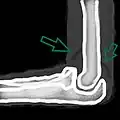

- Skyline view of the patella demonstrating a large joint effusion as marked by the arrow.